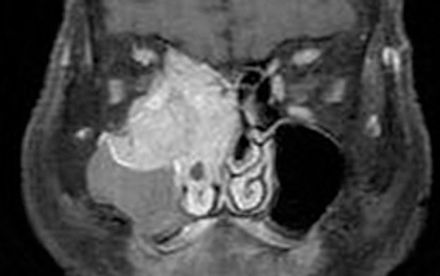

A tumour from the sinus that invades the orbit. Early detection is critical considering the conditions poor prognosis.

Mainly imaging techniques at a sagittal plane which is capable of showing the sinuses.